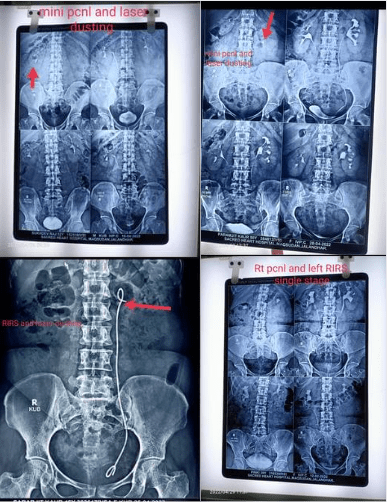

RIRS (retro grade intrarenal surgery) and mini PCNL are being performed regular basis at our Sacred Heart Hospital, Maqsudan, Jalandhar. Currently we are using Holmium laser for the stone fragmentation and dusting. Here are few of the kidney stones done recently with mini PCNL and RIRS laser lithotripsy with complete stone free rates.